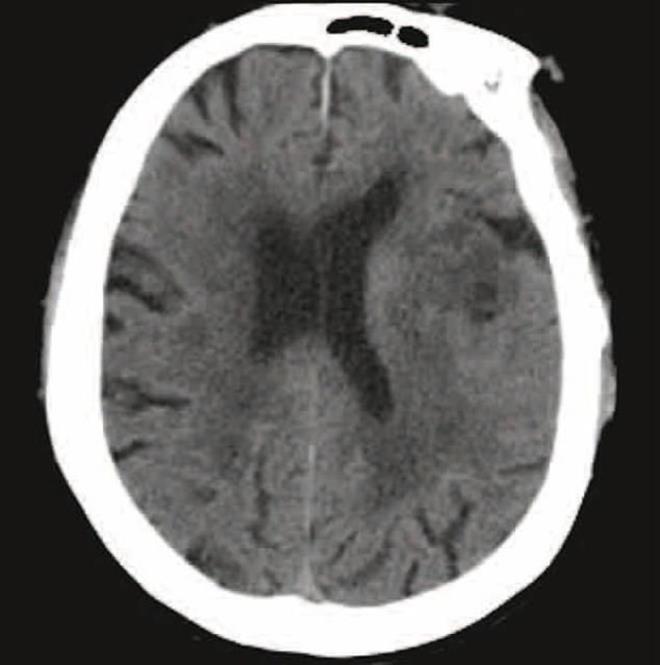

Bir araştırmaya göre yeni tip corona virüs (Covid-19) ağır hastaların yaklaşık yarısında, tüm vakaların ise üçte birinde beyin ve sinir sisteminde hasara neden oluyor. Buradan yola çıkan uzmanlar, salgın esnasında tökezleme, konuşma bozukluğu ya da nöbet geçirme belirtileri gösteren hastalarda Covid-19 testlerinin de yapılması gerektiğini belirtti.

3. NÖROLOJİK SEMPTOMLAR 3 KATEGORİYE AYRILDI  <br>  Uzmanlar görülen nörolojik semptomları üç kategoriye ayırdı; bunlardan birincisi baş dönmesi, baş ağrısı, bilinç bozukluğu, akut serebrovasküler hastalık, atak ve nöbet dahil olmak üzere merkezi sinir sistemiyle ilişkili belirtiler olarak tanımlandı.

Uzmanlar görülen nörolojik semptomları üç kategoriye ayırdı; bunlardan birincisi baş dönmesi, baş ağrısı, bilinç bozukluğu, akut serebrovasküler hastalık, atak ve nöbet dahil olmak üzere merkezi sinir sistemiyle ilişkili belirtiler olarak tanımlandı.

4. Diğer kategoriler ise periferik sinir sistemi belirtileri (tat bozukluğu, koku bozukluğu, görme bozukluğu ve sinir ağrısı) ile iskelet kası yaralanması olarak ikiye ayrıldı.

5. HASTALARINDA YÜZDE 36,4'ÜNDE GÖRÜLDÜ    Araştırmacılar, &#8220;Toplamda 78 hastanın (yüzde 36,4) nörolojik belirtileri vardı&#8221; ifadelerini kullanarak şiddetli enfeksiyonlarda nörolojik belirtilerin artış gösterdiğini söyleyerek şu açıklamayı yaptı:

6. "NÖROLOJİK SEMPTOMLARDA COVİD-19'DAN ŞÜPHELENİLMELİ"    &#8220;Daha ciddi enfeksiyonu olan hastalarda akut serebrovasküler hastalıklar (5'te 1), bilinç bozukluğu (13'te 3) ve iskelet kası yaralanması (17'de 6) gibi nörolojik belirtiler görüldü. Doktorlar, Covid-19 salgını döneminde, nörolojik belirtileri olan hastaları değerlendiririken, ayırıcı tanı olarak yeni tip corona virüs enfeksiyonundan şüphelenmelidir."